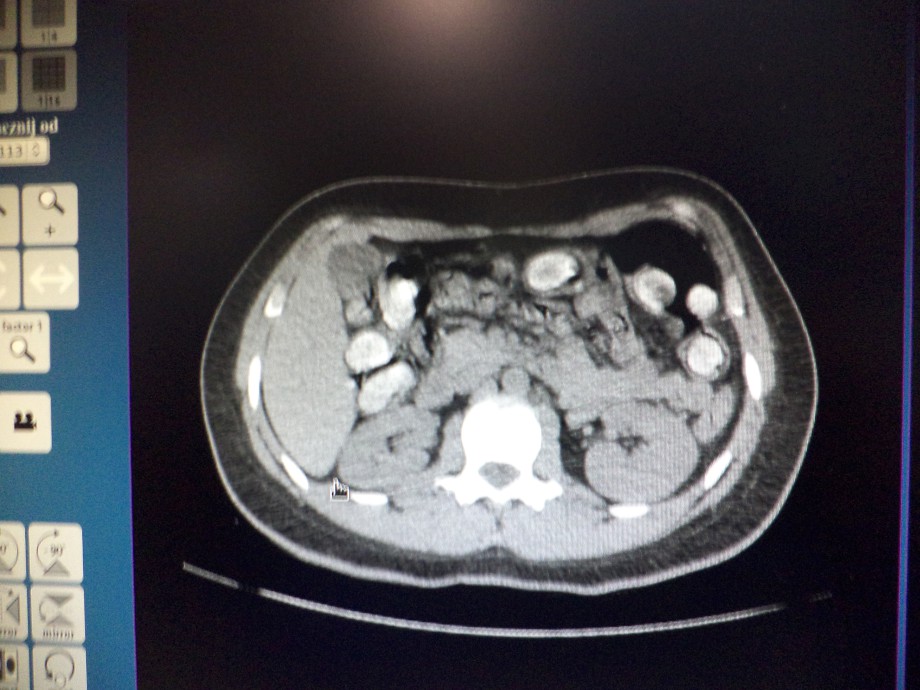

Podróżna została skierowana przez funkcjonariuszy Wydziału Zwalczania Przestępczości Izby Celnej w Warszawie do kontroli celnej z przejścia „nic do zgłoszenia" (tzw. zielonej linii). Zważywszy na czas trwania podróży i przede wszystkim jej kierunek, podróżna została poddana wstępnym testom na obecność narkotyków w ślinie, następnie w moczu. Mimo niejednoznacznego wyniku narkotestów, podjęto decyzję o przewiezieniu podróżnej do szpitala, celem przeprowadzenia badania lekarskiego na obecność narkotyków w organizmie. Wykonane w szpitalu badanie tomografii komputerowej przewodu pokarmowego, potwierdziło podejrzenia funkcjonariuszy celnych, że narkotyki przemycane są wewnątrz organizmu. Podróżna zatrzymana została w szpitalu, celem wydalenia kapsułek z narkotykiem.

Przemycana w żołądku kokaina zapakowana była w 80 kapsułek o łącznej wadze 0,75 kg. Wewnątrz każdej znajdowało się około 9 g narkotyku.